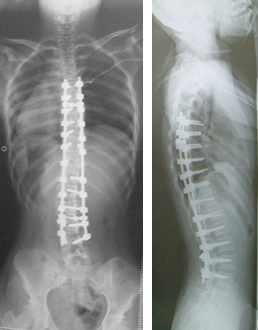

1. 側弯症手術

背中側を切開して椎骨の後方に椎弓根スクリューという金属を挿入して変形を矯正する手術を行います。椎弓根スクリューによる変形矯正は従来の方法に比べ良好な矯正が可能です。ナビゲーションシステムを導入して、正確に椎弓根スクリューを挿入できるように安全対策を行っております。また手術中は常に脊髄に電気を流し、脊髄神経の障害が起きていないかをリアルタイムに確認できる脊髄モニタリングも行いながら手術を行っており、手術治療の安全性はかなり高くなっております。

症例:特発性側弯症